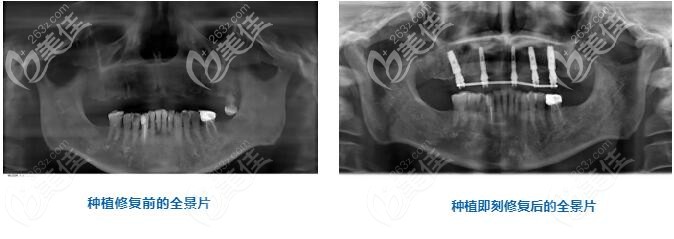

经过姬辉医生一系列的检查后,秦先生的上牙列只留有一只左后牙,虽然戴着活动假牙,但使用不方便,牙槽骨牙龈也已经出现了萎缩。

这种情况下,采用数字化导航种植、数字化修复技术,给秦先生植入5颗人工牙根固定半口牙桥,植体选择的是诺贝尔cc。

从麻醉到导板就位,翻瓣到牙槽嵴修整,备洞,植入种植体,缝合,手术仅用45分钟便就结束,而从手术到戴牙也仅仅只用了3个小时。

术后即刻全景片的对比能直观的看出来,上半口缺失的牙齿已经被种植体所取代。